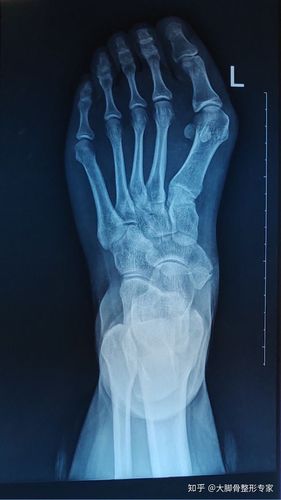

大脚骨和小脚骨x光片